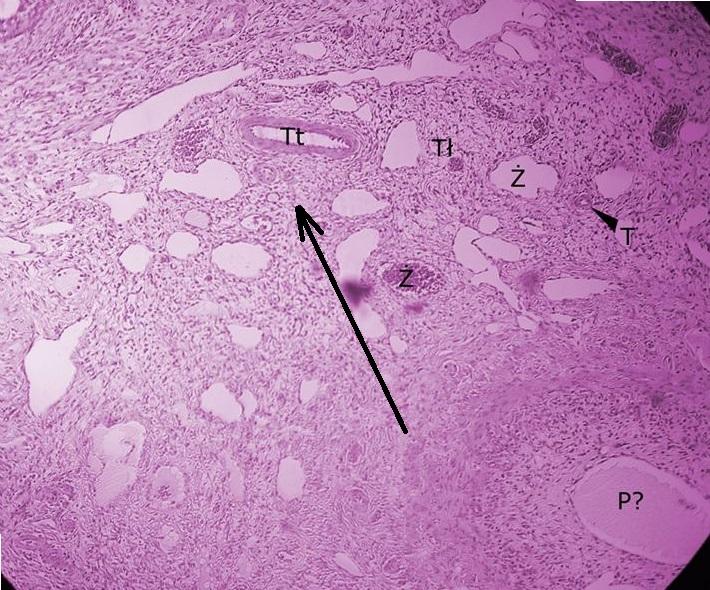

tkanka łączna w rdzeniu jajnika - rdzeń poznajemy po dużej ilości tkanki łącznej i naczyń krwionośnych, a także po braku pęcherzyków (jajnik)

Pytanie 666

tętniczka (jajnik)

Pytanie 667

żyły (jajnik)